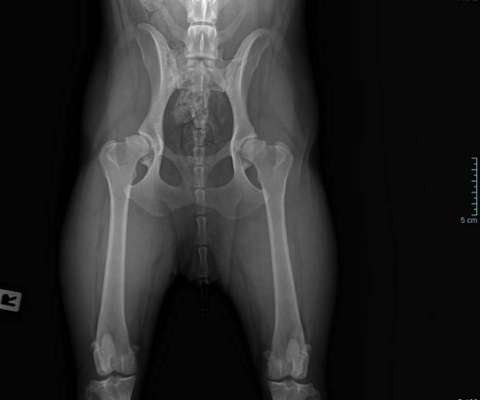

Rechte Seite schlimmer

Seitliche Aufnahme mit spondylose

Ja, mithilfe spezieller Messungen kann der Grad der HD anhand des Röntgenbildes beurteilt werden.

Okay, das wurde vom Tierarzt nicht gemacht.

Was denken Sie anhand des Röntgenbildes?

Anhand des Röntgenbildes (ich bin keine anerkannte geprüfte Expertin) handelt es sich um eine fortgeschrittene Dysplasie des rechten Hüftgelenks. Ist das Video unter Medikamentengabe entstanden oder von vorher?